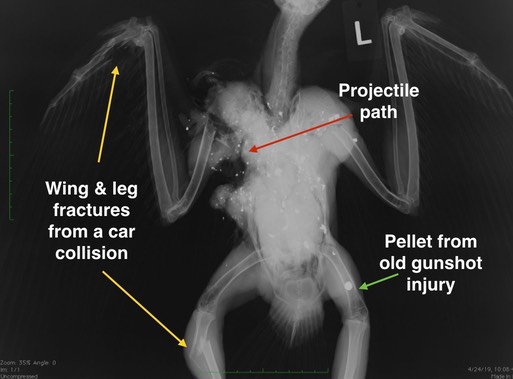

More Gunshot Birds

Washington Department of Fish and Wildlife asked BMW to radiograph an adult Swainson's Hawk that was found dead, hanging in a tree near Walla Walla. The radiograph told a very sad tale. It appears that the hawk was hit by a car, fracturing the metacarpals in the right wing and the tibiotarsus in the right leg. The hawk was then able to fly well enough to get up into a tree near the road. A short time later, she was found dead, hanging in the tree, having been shot. The (round) pellet seen in her left leg had been in her leg long enough for signs of injury to heal, indicating she had recovered from her first gunshot injury.